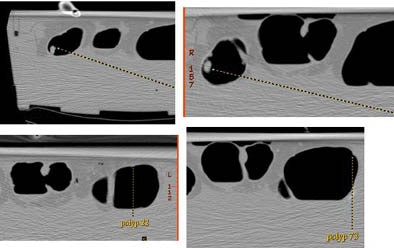

![]() |

| Each of the 21 polyps in the specimen was matched and measured with the CT data, but at half distension (left) and full distension (right) on both 2D and 3D views. |

The combined observer Bland-Altman 95% limits of agreement were similar for both datasets (half distension: 2D -3.7 mm to 1.5 mm, 3D -2.9 to 1.6 mm; full distension: 2D -3.8 to 1.3 mm, 3D -2.9 to 2.8 mm).

"We can see that 3D is more accurate than 2D in the half distension, and similarly in the full distension 3D was more accurate than the 2D measurements," Taylor said. The technologist didn't do quite as well as the trained radiologist but the trends were the same, he added.